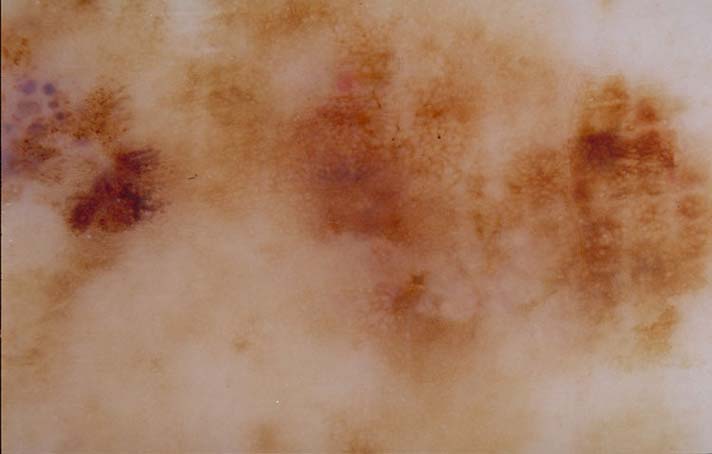

| 153 "diagnosis.char"="Melanocytic leison" "comment.char"="" "features.char"="Pigment network - pseudonetwork (see exception 1)" | "diagnosis.char"="Lentigo maligna" "breslow_depth.float"="0" "comment.char"="Note prominent follicular plugs." "features.char"="Asymmetric pigmented follicular openings|Blue-white veil|Rhomboidal structures|Scar-like depigmentation" |  |  |